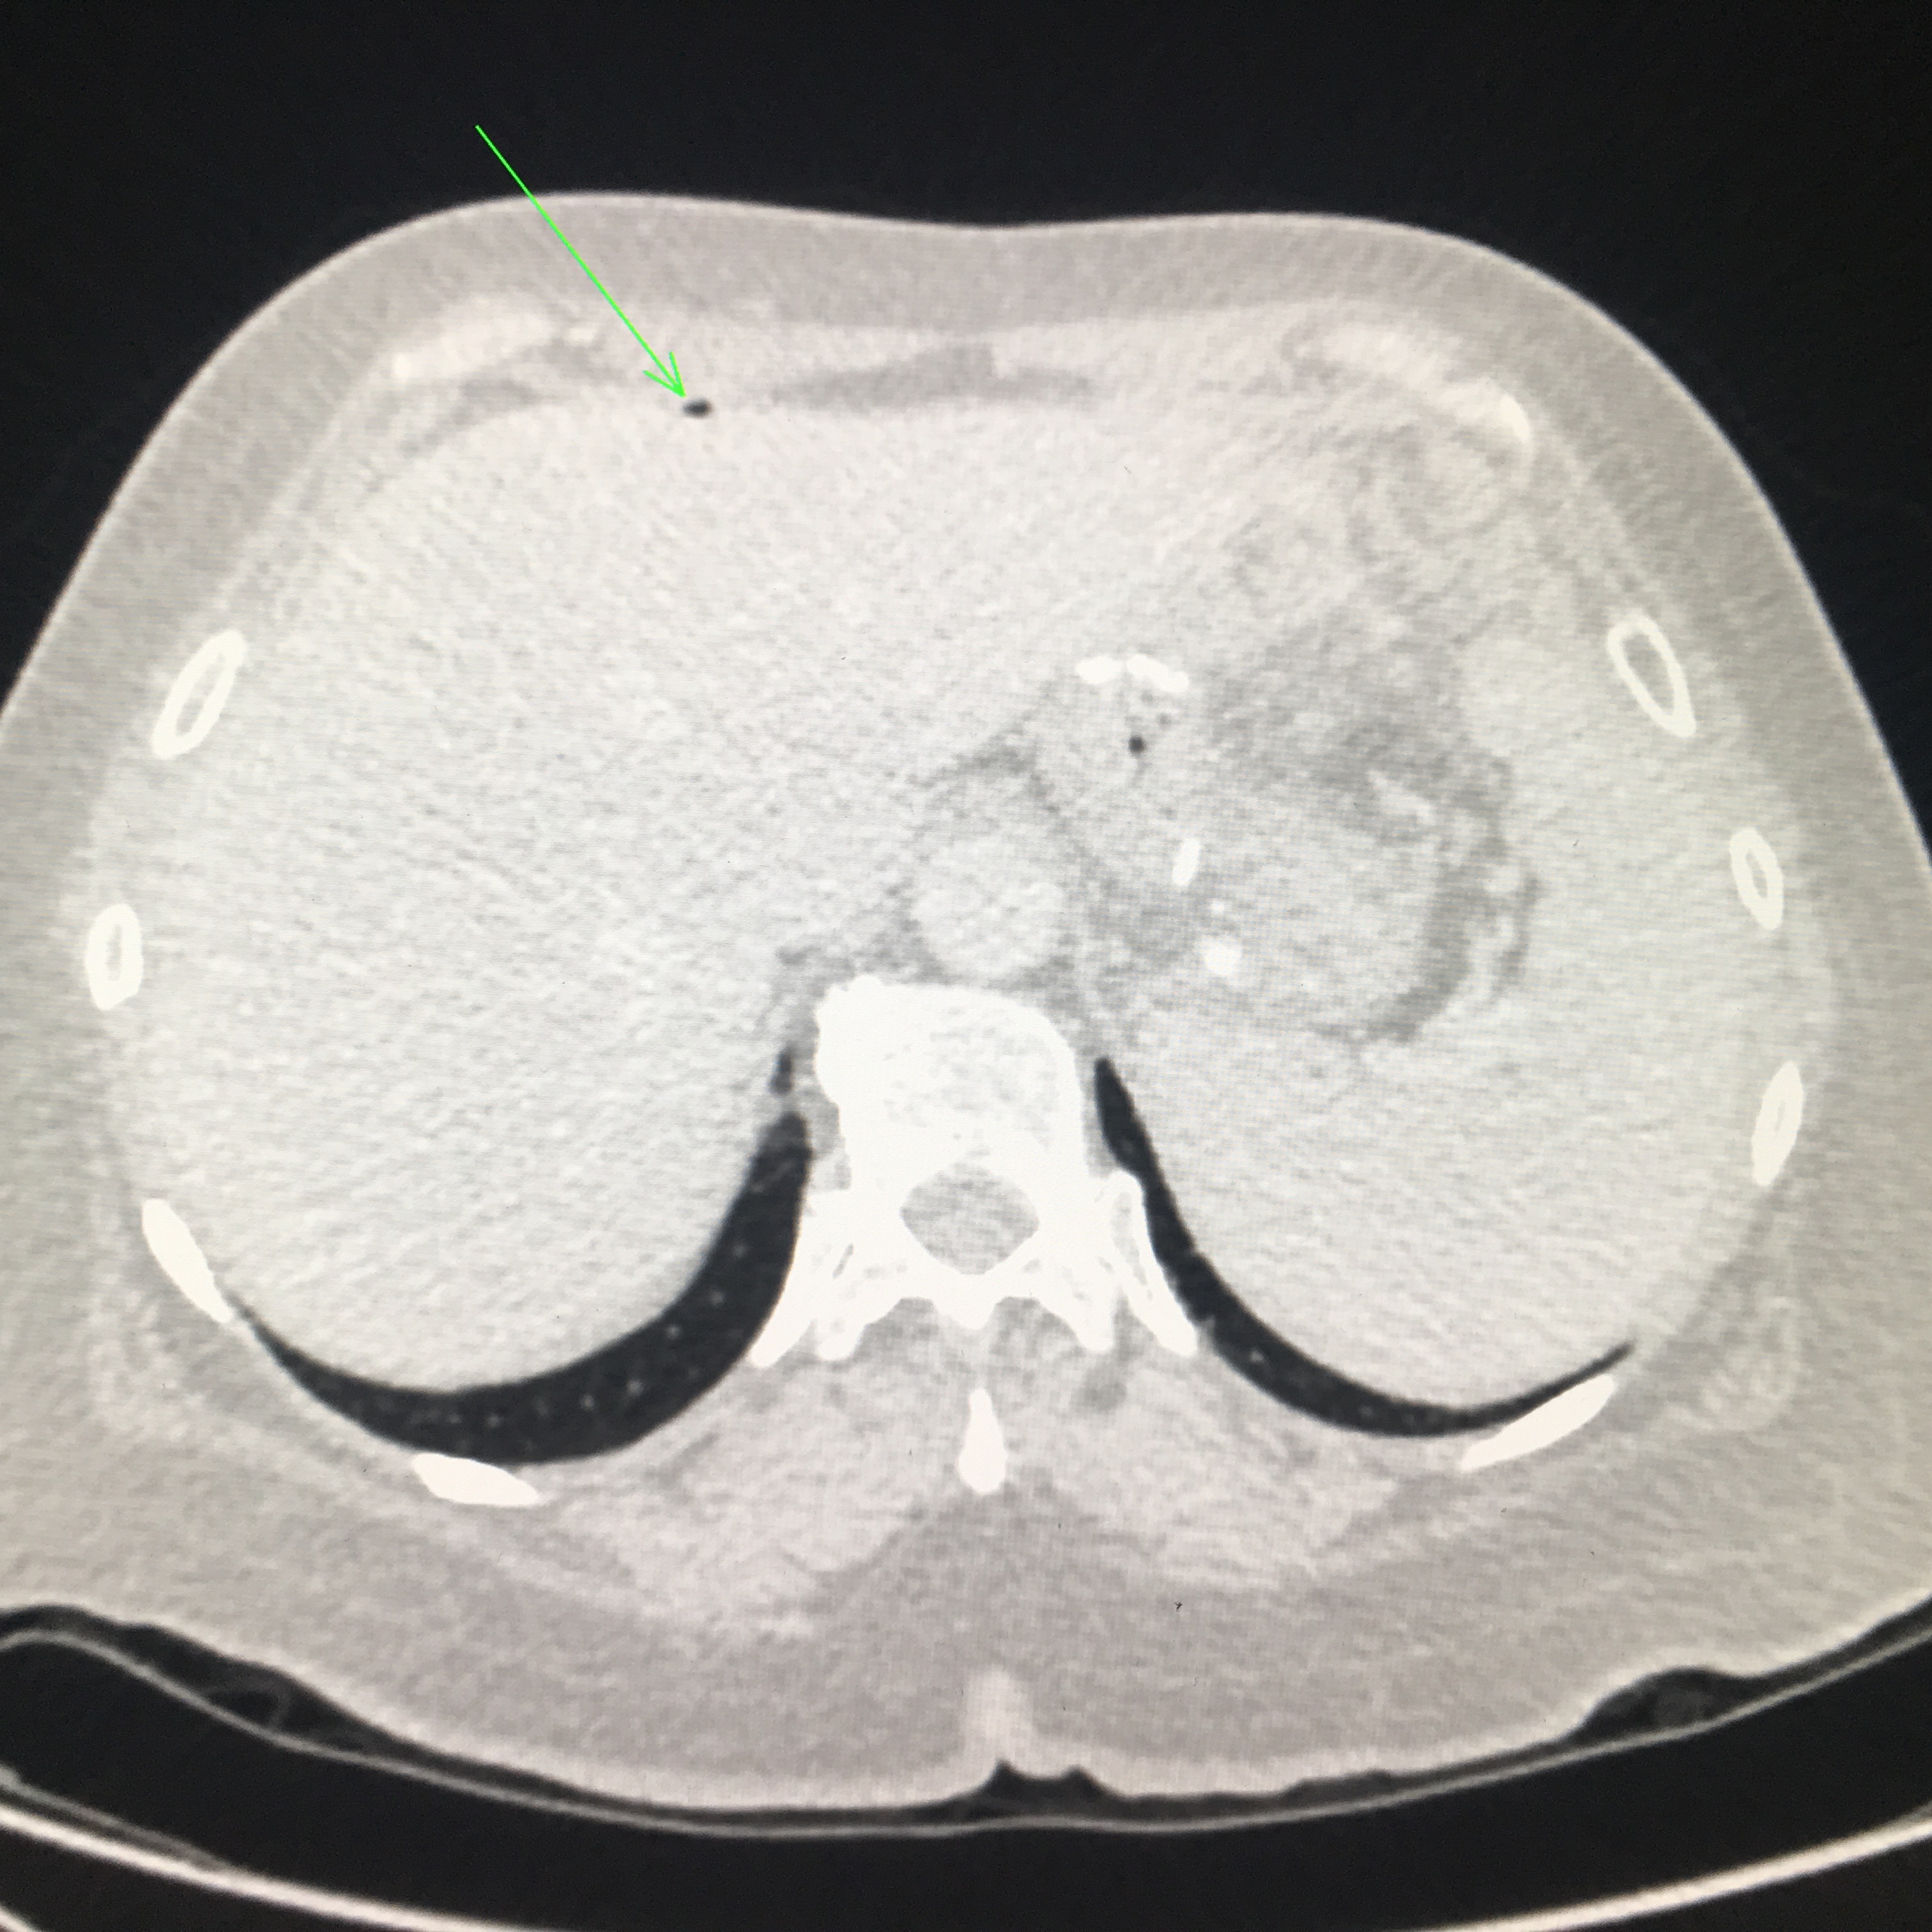

CT views demonstrating two small pockets of intraperitoneal free gas anterior to the left lobe of the liver as indicated by the green arrows.

The report confirmed the presence of a small amount of free intraperitoneal gas anterior to the liver and below the left hemidiaphragm. Additionally, there were two ill-defined rounded masses with peripheral enhancement, low attenuation centres and some adjacent streaky perilesional soft tissue at the left gastrocolic ligament and abutting the lateral left hepatic lobe and left hemidiaphragm. The CT report concluded these soft tissue abnormalities were abscesses secondary to recent gastric perforation with a differential of disseminated malignancy.